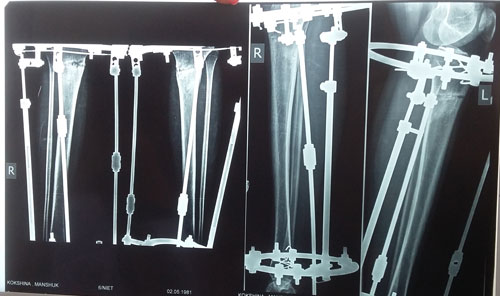

В процессе исправления деформации.

Сегодня 90 дней с момента ОП.

Отправляю Вам фото рентген снимков.

Посмотрите пожалуйста состояние?

Можно ехать?

С нетерпеньем жду, спасибо.

Здравствуйте, М.! Сращение хорошее, ждём на снятие аппаратов через 2 недели.

Дата операции 25.03.2015г.

Дата снятия аппаратов 10.07.2015г.

Срок лечения 105 дней.

рентген контроль в 1,5 месяца с момента снятия аппаратов.

Здравствуйте, Моня! Сращение отличное! Вам разрешено все без ограничений, спорт, каблуки и т.д. Живите полной жизнью и радуйтесь красоте Ваших ног!